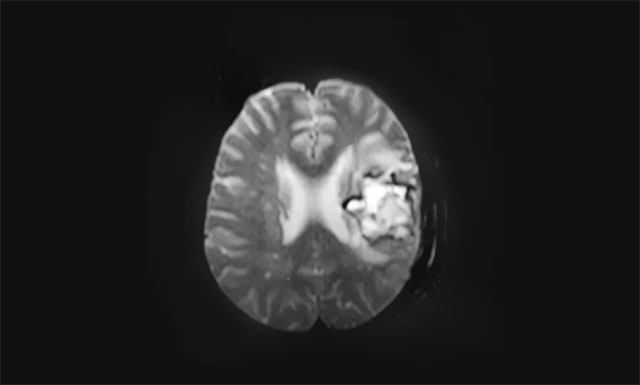

39的小徐(化名)既往有高血壓、冠心病多年,血壓最高達(dá)收縮壓180mmHg,舒張壓100mmHg。正值壯年的他從事財(cái)務(wù)工作,他是家中的頂梁柱,家有愛妻和兩個(gè)孩子,一家...[詳情]